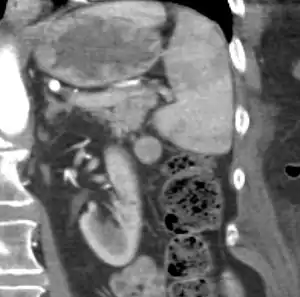

Gross pathology of an accessory spleen

If splenectomy is performed for conditions in which blood cells are sequestered in the spleen, failure to remove accessory spleens may result in the failure of the condition to resolve.[1] During medical imaging, accessory spleens may be confused for enlarged lymph nodes or neoplastic growth in the tail of the pancreas,[5] gastrointestinal tract, adrenal glands or gonads.[2]